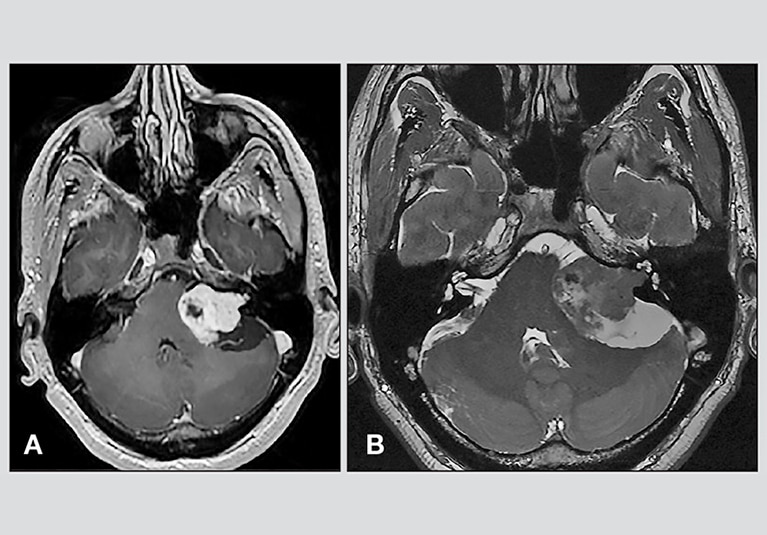

另外听神经鞘瘤过大,还会压迫到小脑以及脑干这些重要组织及周边血管,而手术一旦出现过大损伤,都足以对病人造成严重致残或生命威胁。所以听神经鞘瘤的手术操作,就要求在这些神经、血管和重要脑组织间隙进行操作。对外科医生的手术操作技术水平提到了一个很高的水平。从这个范畴上来讲,听神经鞘瘤属于大手术范畴。

对于听神经鞘瘤的显微手术治疗,常用的手术入路有三种:经乙状窦入路(retrosigmoid,RS),也称经枕下入路,经迷路入路(translabyrinthine,TL),经颅中窝入路(middle cranial fossa,MCF)。3种入路各有优缺点,具体选择哪种手术治疗方案要依据患者的年龄、听力情况、肿瘤体积的大小等方面综合考虑。其中RS入路几乎适用于各种大小的听神经鞘瘤,其优点是快速、直接暴露CPA区,易于掌控局部神经血管结构,易于剥离肿瘤,及早保护脑干,并且有利于面神经功能及听力的保留;其缺点是常见术后头痛,对内耳道底暴露不充分。TL入路及MCF入路则更适合于某些少数听神经鞘瘤患者。TL入路适用于较小肿瘤,其优点是提高了保留听力可能性,其缺点是局部操作复杂。